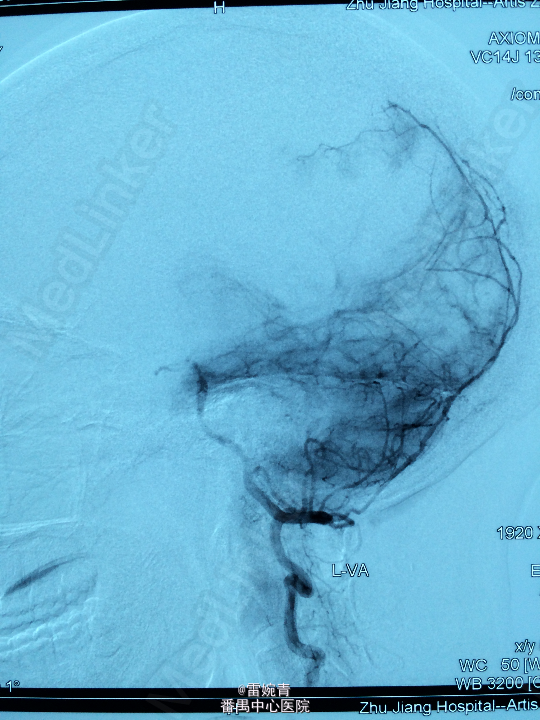

诊断:脑膜瘤 处理:先行DSA检查以明确脑膜瘤的供血动脉情况,见:肿瘤染色,肿瘤主要由左侧眼动脉供血,用Glubran胶将其闭塞,后择期行手术切除治疗。术后病理证实为脑膜瘤。